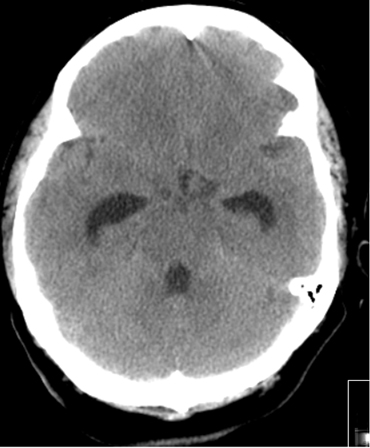

Subarachnoid hemorrhage

Communicating hydrocephalus in the setting of subarachnoid hemorrhage; note dilation of fourth and temporal horns of lateral ventricles

Courtesy of Dr Salah Keyrouz; used with permission